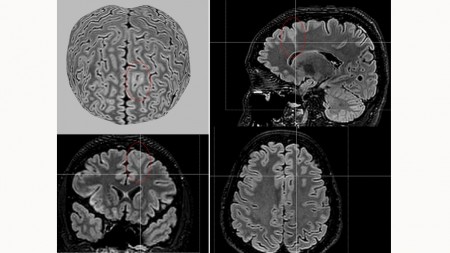

A partir de técnicas de aprendizado de máquina e da análise de dados de ressonância magnética de 1.185 participantes – incluindo 703 pessoas com displasia cortical focal e 482 controles – a ferramenta, denominada MELD Graph, conseguiu detectar as anormalidades a partir de varreduras nas imagens cerebrais.

A ferramenta, cujo algoritmo está disponível publicamente, detectou 64% das anormalidades cerebrais ligadas à epilepsia que os médicos radiologistas não haviam detectado. Com isso, a expectativa é que a MELD Graph possa atender a mais de 4 milhões de pessoas em todo o mundo que convivem com esta causa de epilepsia.

O desenvolvimento da ferramenta de IA ficou a cargo de pesquisadores do King’s College London e do University College London, ambos do Reino Unido. Já as imagens de ressonância magnética de alta qualidade foram fornecidas por 23 centros de pesquisa em epilepsia em todo o mundo que fazem parte do consórcio. O Instituto Brasileiro de Neurociência e Neurotecnologia (BRAINN) foi uma das instituições com alta capacidade de captação e análise de imagens a fornecer dados para o projeto.